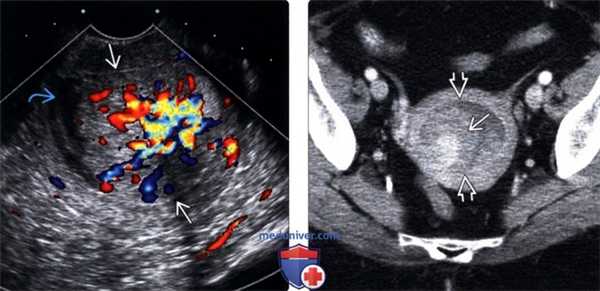

(Слева) Трансвагинальная цветовая допплерография в поперечной плоскости: визуализируется гиперваскулярное эхогенное объемное образование, растягивающее полость матки, которое по результатам патологического исследования было диагностировано как рак эндометриоидного типа. Прорастание миометрия на УЗИ выявлено не было. Имеется незначительная гематометра.

(Справа) КТ, поперечный срез: у этой же пациентки определяется накапливающее контраст объемное образование эндометрия внутри растянутой полости матки. Лимфаденопатия не выявлена.